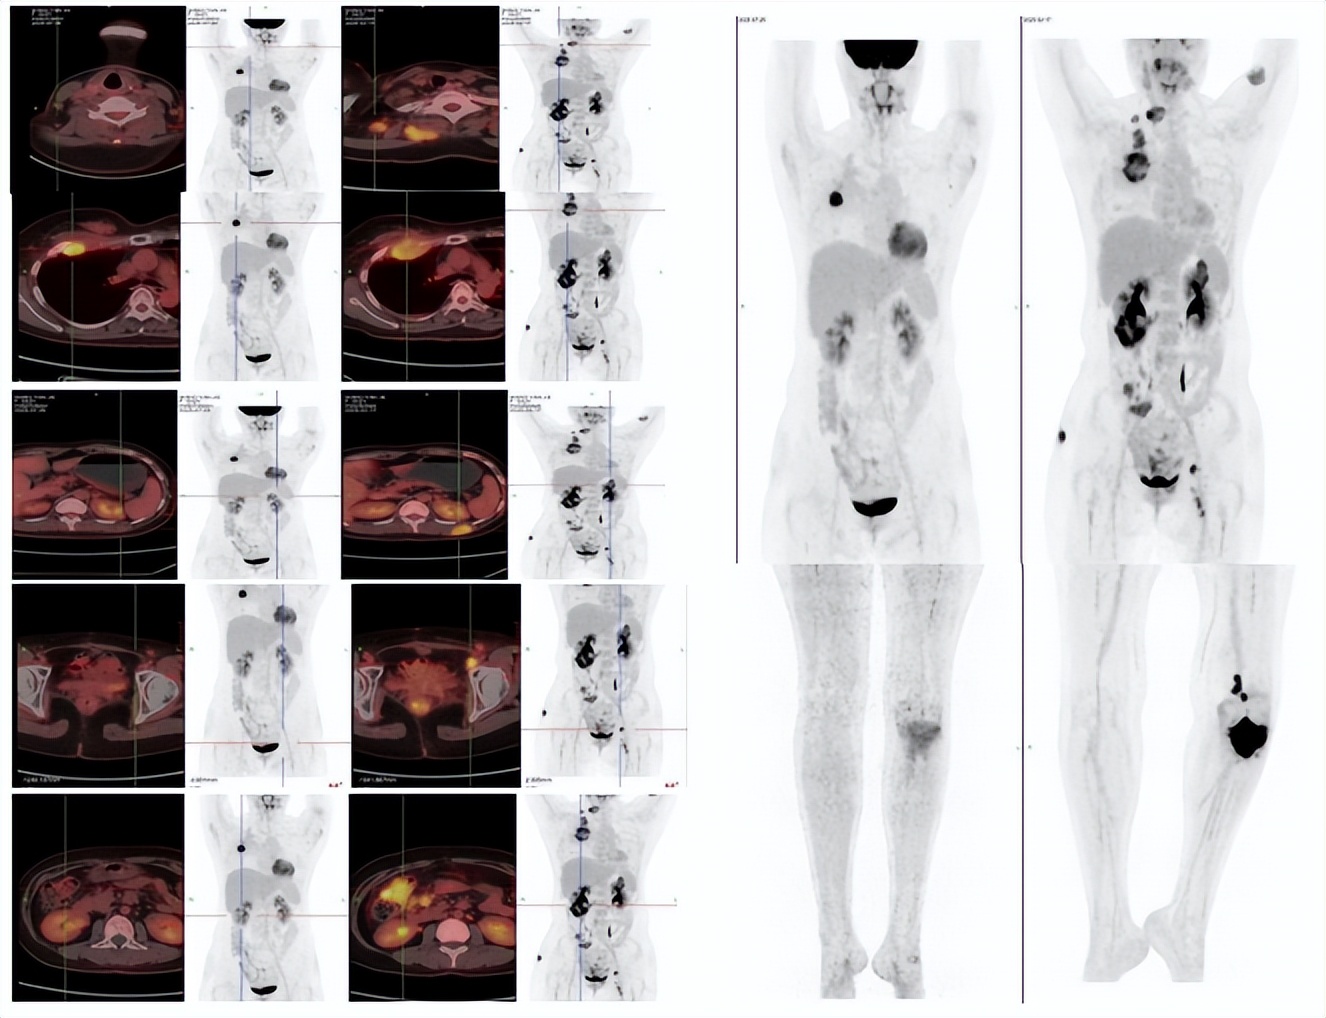

患者经上述治疗两周期后腹部及骨痛症状完全缓解,能独立行走,治疗过程中出现脱发,II度骨髓抑制,未出现其他明显的治疗相关不良反应。2025年07月PET-CT复查评估提示较前显著好转(图2),肿瘤指标降至接近正常水平(图3),总体评价PR,PFS超过6月。

PET-CT:布拉格5月后(2025.07)基线(2025.02)

(左:基线;右:布拉格3周期治疗后)

图2:PET-CT、肉眼可见皮肤转移灶提示较前显著好转